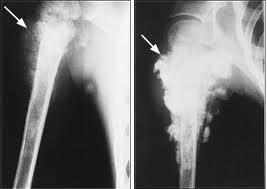

A csontrák olyan daganat típus, mely általában a csont felszínén keletkezik, és onnan terjeszkedik a csont belseje felé. A kialakulás pontos oka sajnos még nem ismeretes.

A csontrák tünetei leggyakrabban a daganat helyének közelében jelentkezik. Ez jellemzően a végtagok, bokájuk, és térdük környéke, de előfordulhat még többek közt a bordáknál, illetve az orrüregben is. A tünetek a daganat elhelyezkedésétől függően változhatnak. Lehet az adott helyen csontnagyobbodás, látványos duzzanat, ha a végtagok érintettek ízületi fájdalom, sántítás, orrüreg esetén tüsszögés, orrvérzés, nehézlégzés.

A kezelés hatékonysága számos tényezőtől függ, többek közt, hogy a daganat milyen mélyen helyezkedik el a csontban, illetve már elérte-e a csontvelőt.